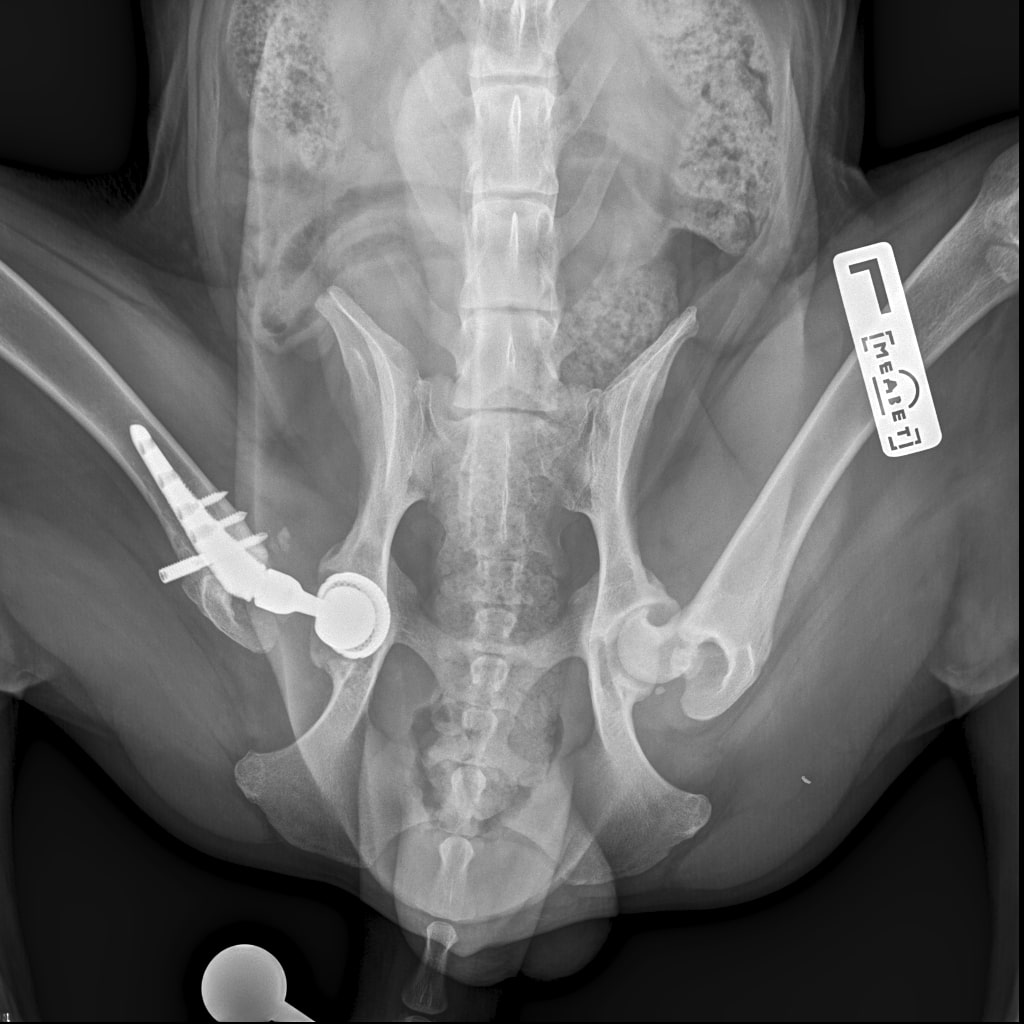

8A836050-66CA-42B2-94D3-F13B288A592B.jpeg

39B2671E-39B9-4502-9E11-ADB169612F24.jpeg

6950B9C9-79EA-4F34-A780-9C3C6BA31B49.jpeg

58C20B18-AA4E-4386-BF83-56CE5E282844.jpeg

Наш металлический мальчик

Железный дровосек